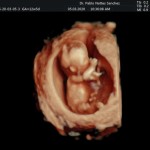

- Las Estructuras Anatómicas Fetales, diagnóstico precoz de Malformaciones Severas importante mencionar que las malformaciones pequeñas y moderadas solo podrán ser detectadas entre la 18va a 22da semana de gestión (5to mes).

- Los Marcadores Cromosómicos y determinación de riesgo para trisomías (Rastreo de S. Down y otros con una sensibilidad del 85 a 90%).

- El escenario Gravídico: Placenta, liquido, Cérvix y Anexos.